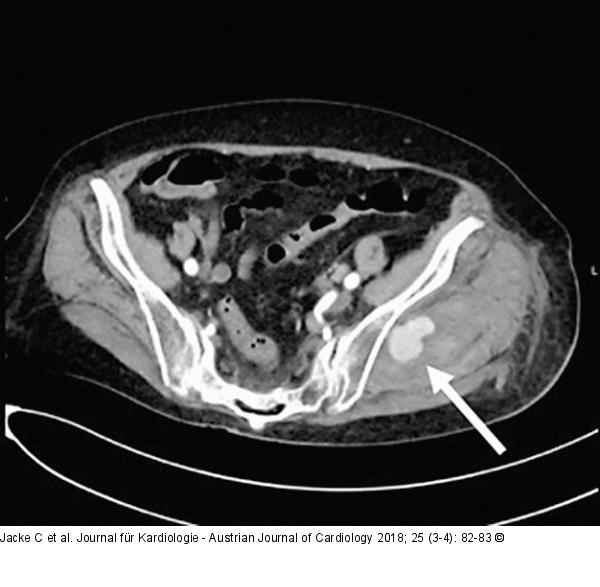

Abbildung 1: Persistierende Blutung

Angio-CT zeigt die persistierende Blutung (weißer Pfeil) aus der linken Art. obturatoria. |